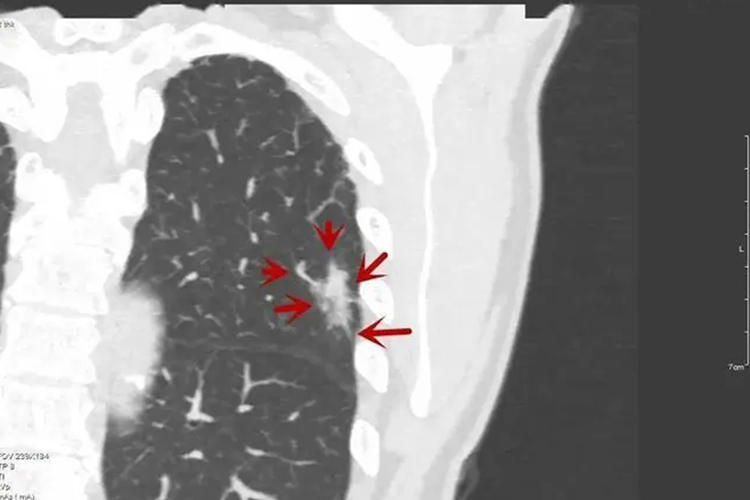

大多数良性肺结节的形态为圆形或类圆形,与恶性实性结节相比,恶性肺结节出现不规则形态的比例较高;毛刺征、分叶征常提示恶性的可能,而良性肺结节多数无分叶,边缘可有尖角或纤维条索等,周围出现纤维条索,胸膜增厚等征象;病灶周围的胸膜凹陷征与血管集束征亦为鉴别良恶性常见且有价值的特征。